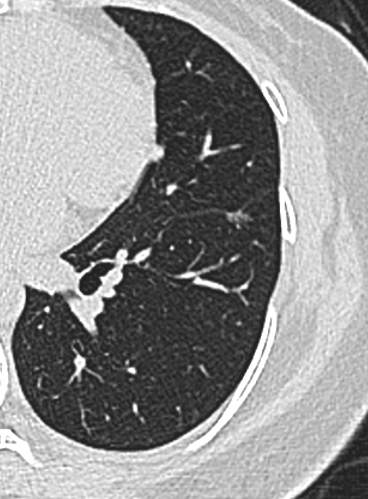

23年初复查CT左下肺GGO有所增大,直径:6.9mm

img

问题来了,一年多后复查GGO有增大,考虑恶性吗,需要手术吗,病理考虑什么?